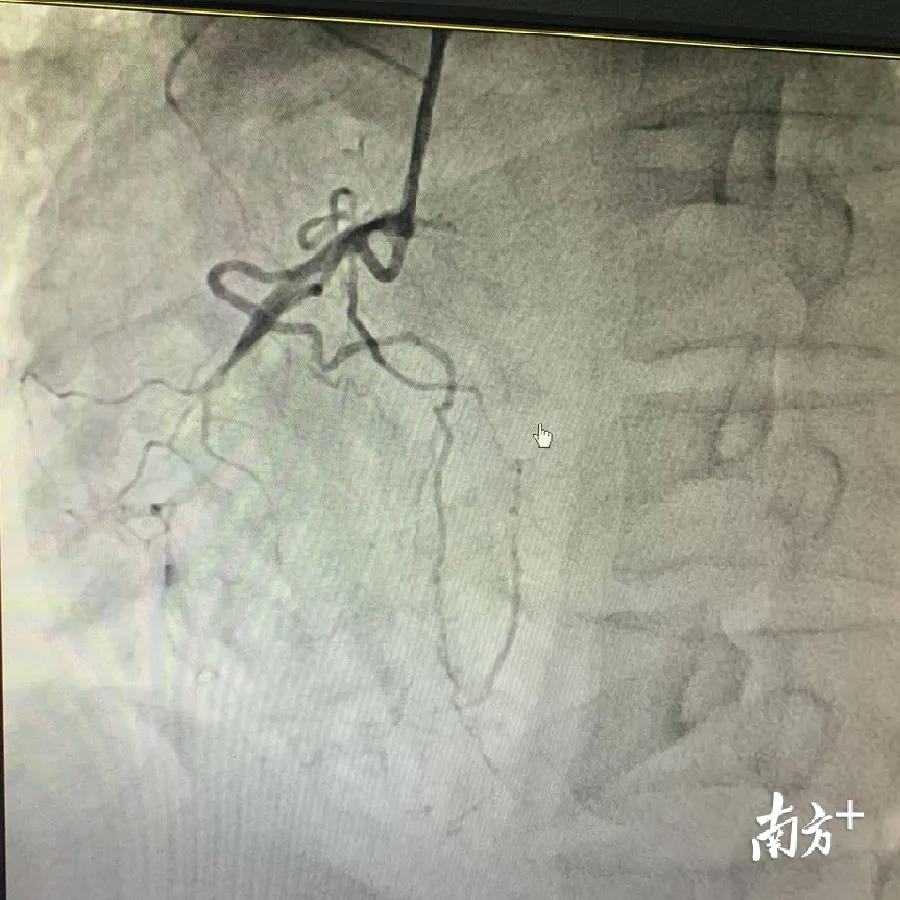

为了更加准确判断钱先生的病情,兰军为钱先生进行抗心衰治疗后,为患者行冠状动脉造影术。当他看到钱先生的心脏血管的情况时,兰军脸色变得十分严峻:造影术显示左前降支近段完全闭塞;回旋支远端重度狭窄,右冠状动脉中段慢性完全闭塞。

“钱先生三条大的冠状动脉堵塞了最大的两条,剩下的一条动脉随时有可能堵塞的状态,心血管堵塞程度十分严重。”兰军说,目前最有效的方法是争分夺秒打通闭塞的血管。但是,因钱先生的病情危重,手术的死亡率有可能达到80%以上!